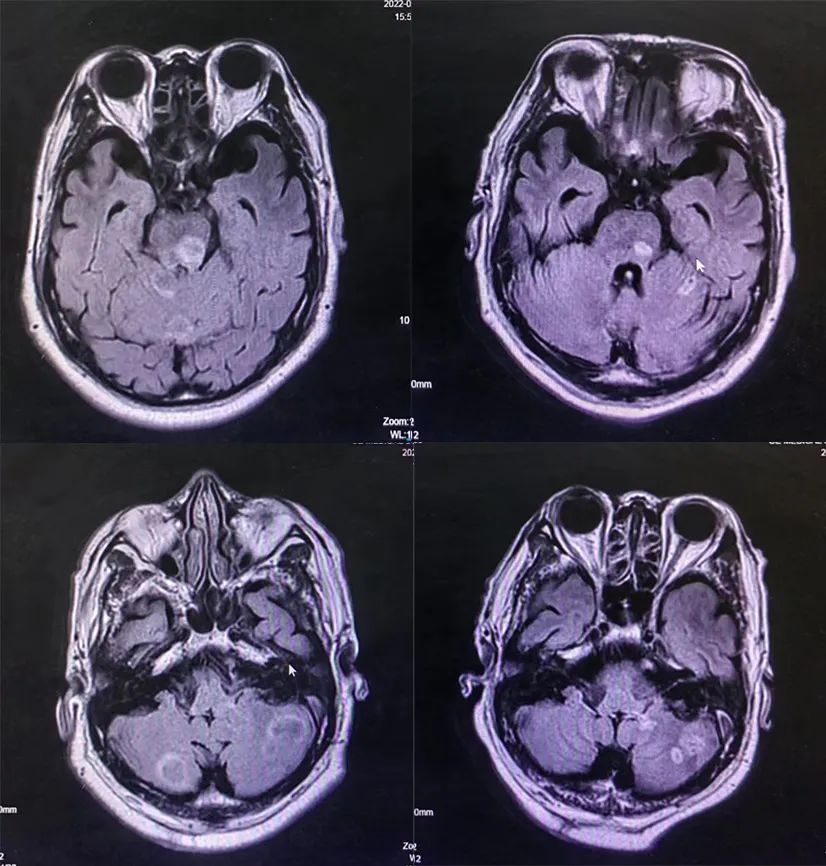

2021-05-31颅脑MRI:脑内多发转移瘤(最大者居于左半卵圆中心,约12×14mm),脑内多发缺血灶。

图4.二线治疗前颅脑MRI结果

2022-03-21颅脑MRI:脑内多发转移瘤复查,较前数量增多,体积增大。

颅脑MRI评估:

对比2022-03-21 MRI脑内多发转移瘤较前减少、减小;双侧大脑白质区及小脑半球、脑干见多发大小不等稍长T1稍长T2信号灶。DWI大部分呈低信号,部分呈环形略高信号,增强后病变未见明显强化,较前减少、减小。

三线治疗疗效评估:颅脑PR、原发灶SD